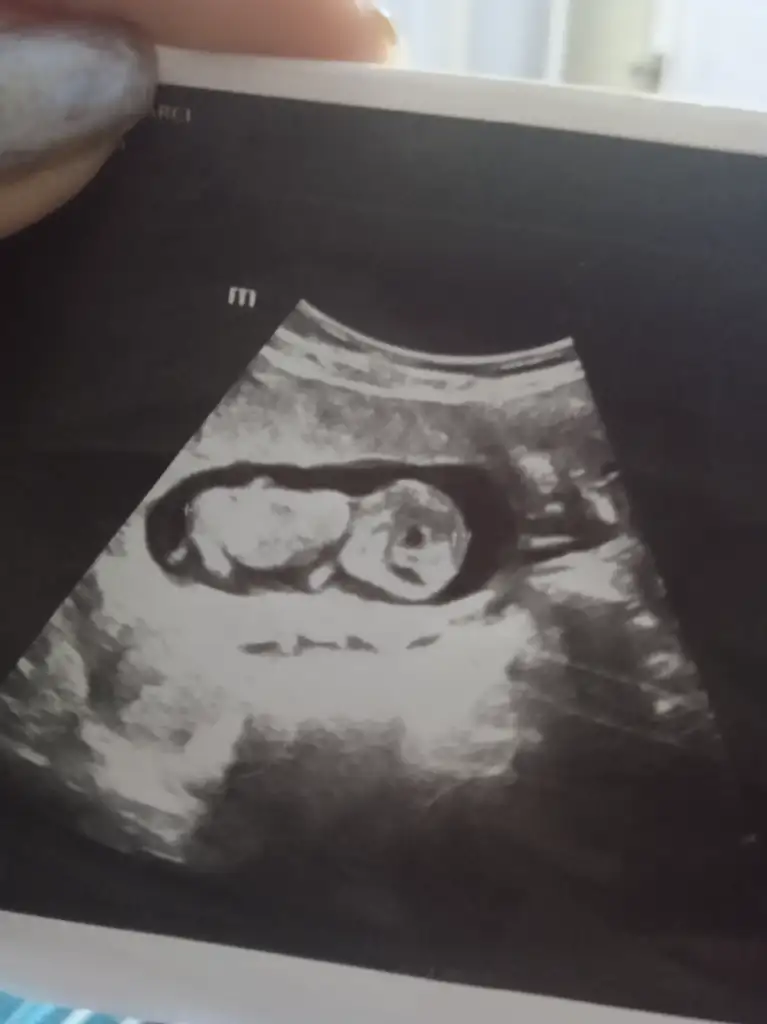

Bna bakrmsnKesinlikle kızz![]()

Ramzi teorisine göre de erkekbu teoriler sende tutmayacak sanırım

KizArkadaşlar tahmin edebilen var mi